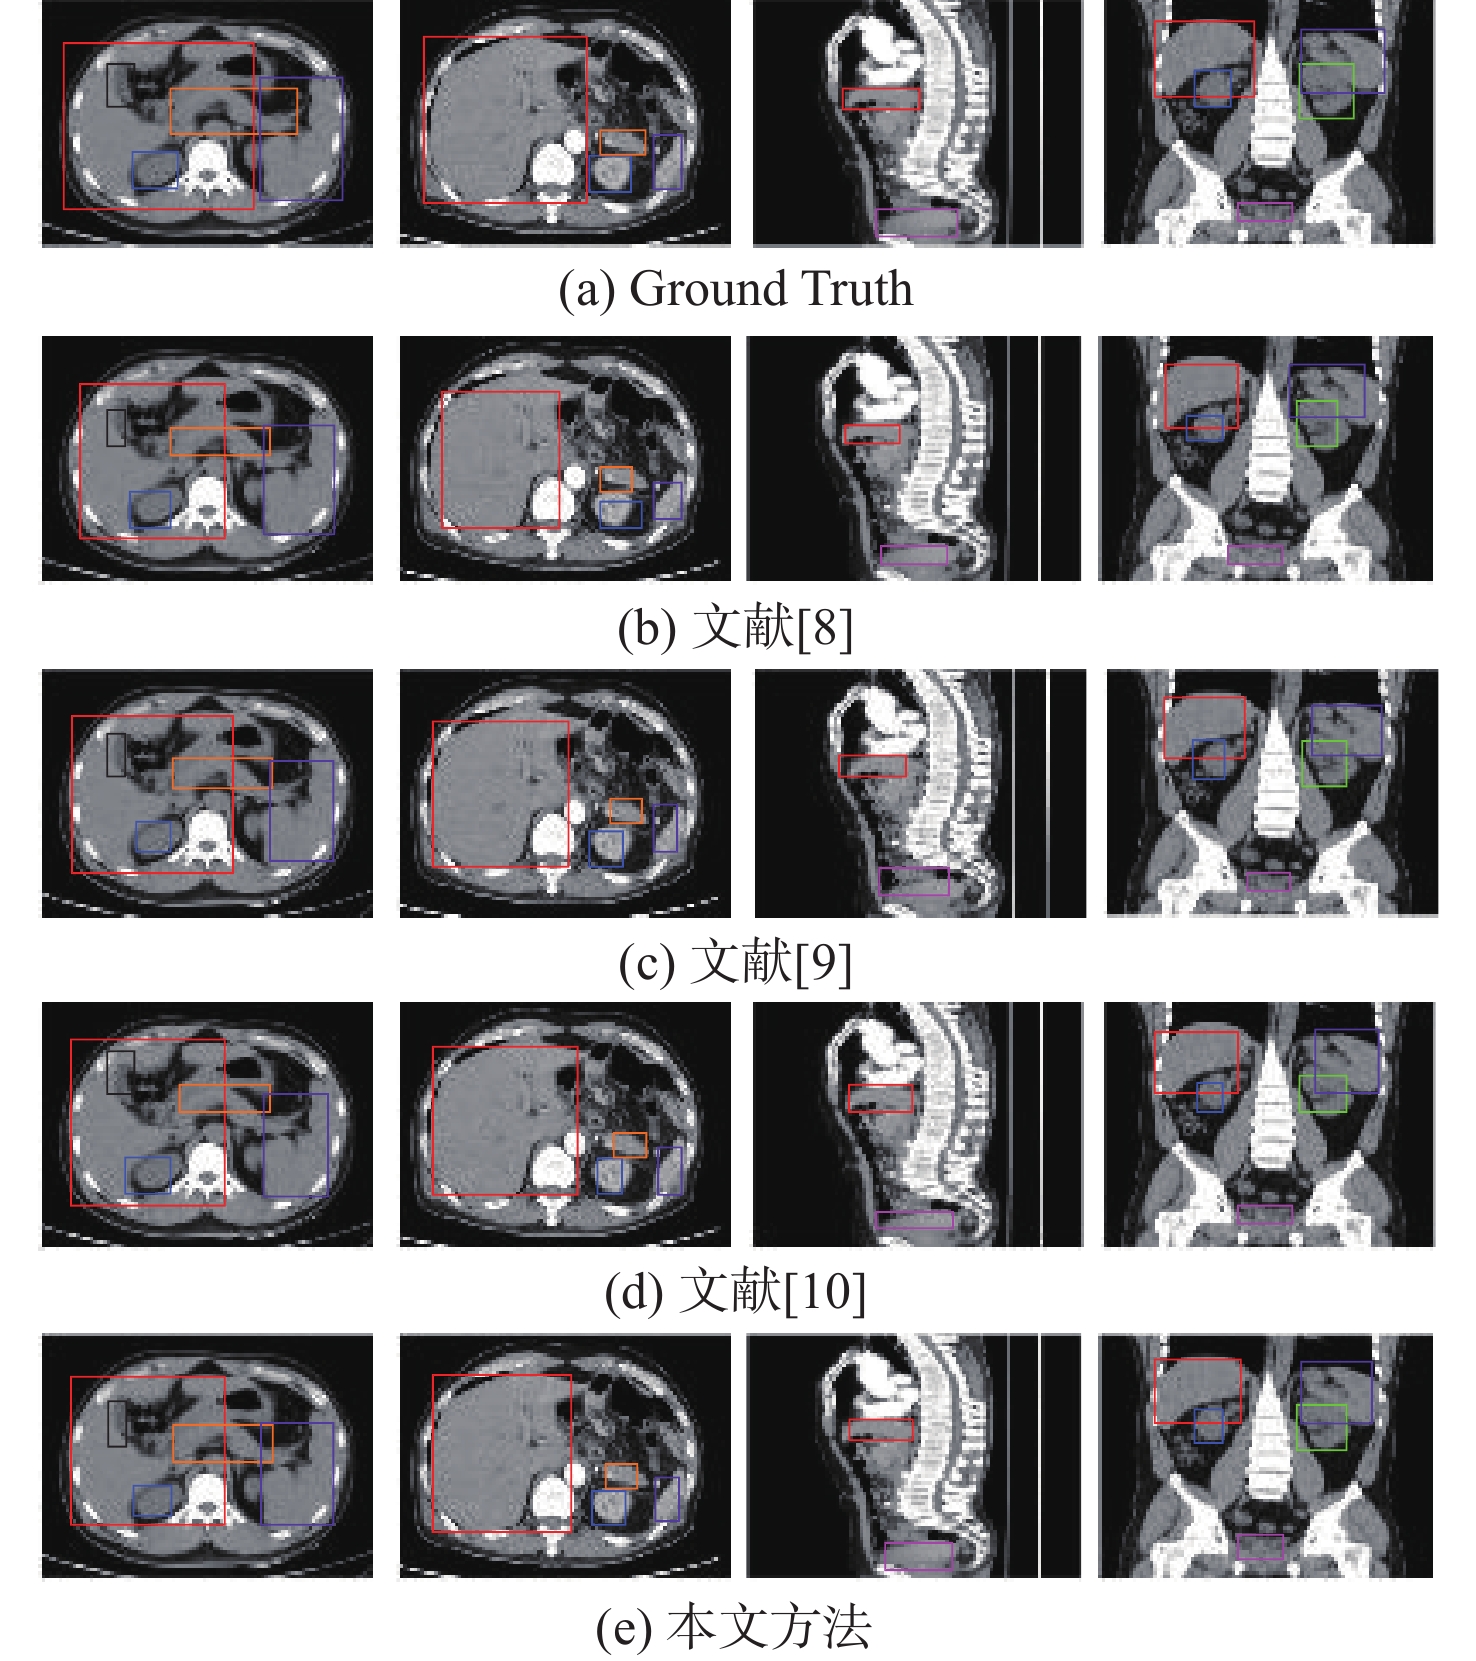

A low-dose CT deep unfolding network based on a sparse transform priors constrain

WANG Yue, ZHANG Xiong, SHANGGUAN Hong, CUI Xueying, ZHANG Pengcheng, GUI Zhiguo

2026, 52(4): 1199-1210. doi: 10.13700/j.bh.1001-5965.2024.0049

Abstract:

Deep iterative unfolding networks have garnered a lot of attention lately because of their great learning capabilities and good interpretability. The regularization terms in existing CT image reconstruction methods mostly focus on information within a specific domain, leading to issues such as edge blurring and information loss in the reconstructed results. Therefore, a sparse transform prior constrain based deep unfolding network is proposed for sparse-view CT reconstruction. Two regularization terms with complementary information—transform-domain sparse regularization and pixel-domain consistency regularization—are created in consideration of the important roles that both pixel-domain and transform-domain information play in picture reconstruction. Based on these, the objective function for sparse-view CT reconstruction is redesigned. Furthermore, a new deep unfolding network for iterative reconstruction of low-dose CT is created by mapping a set of constraint relationships established from an iterative optimization solution for the constructed objective function. Experimental results demonstrate that the algorithm presented in this paper achieves a great improvement on average peak signal to noise ratio (PSNR) and visual information fidelity (VIF) compared to the classical FISTA algorithms.